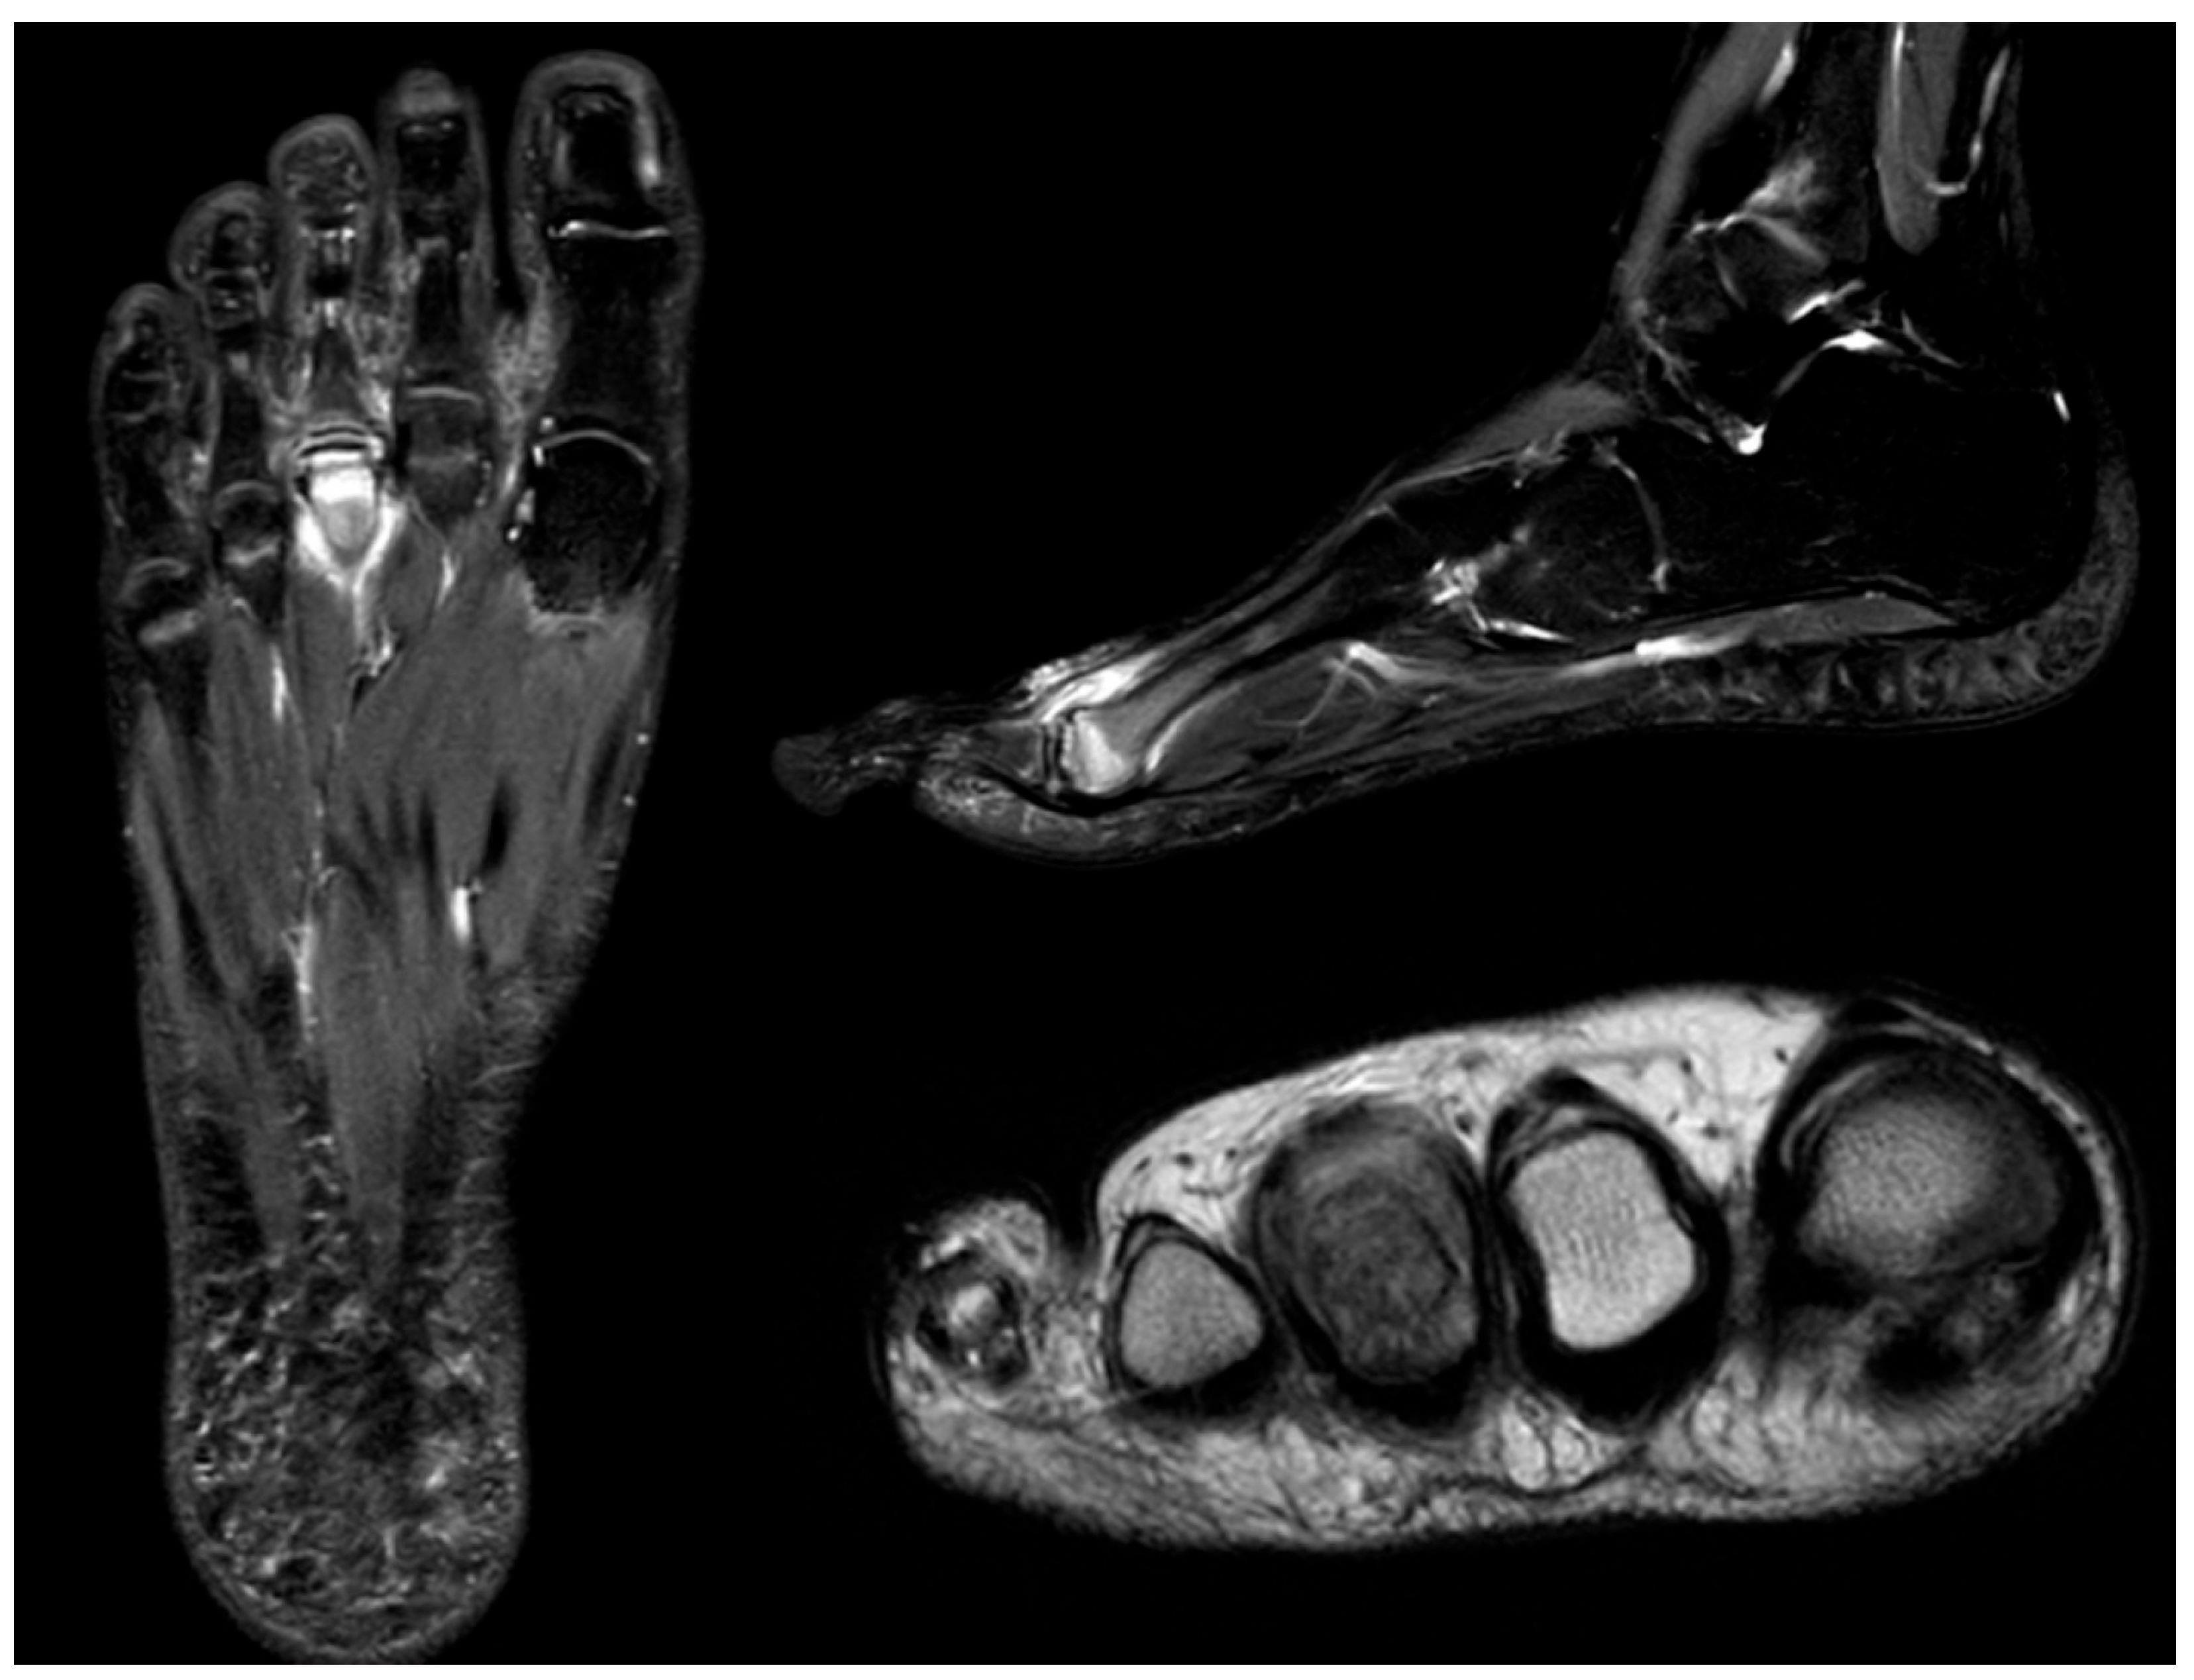

Standard radiographs and Computer Tomography (CT) scans commonly demonstrate a well-ossified accessory bone adjacent to the proximal medial margin of the navicular (Figure 17). In some cases, the accessory navicular is not only a source of localized symptoms but may also predispose the tibialis posterior tendon to chronic or acute injury. Tendinous fibers usually insert onto both the navicular and the accessory ossicle, and this atypical anatomy may increase the risk of tendon dysfunction, particularly in athletes. MRI in such individuals may reveal edema within the accessory navicular, indicative of chronic mechanical stress and overuse [63] (Figure 18).

Figure 18.

MRI of an 11-year-old symptomatic female patient showing bone marrow edema within the accessory navicular.